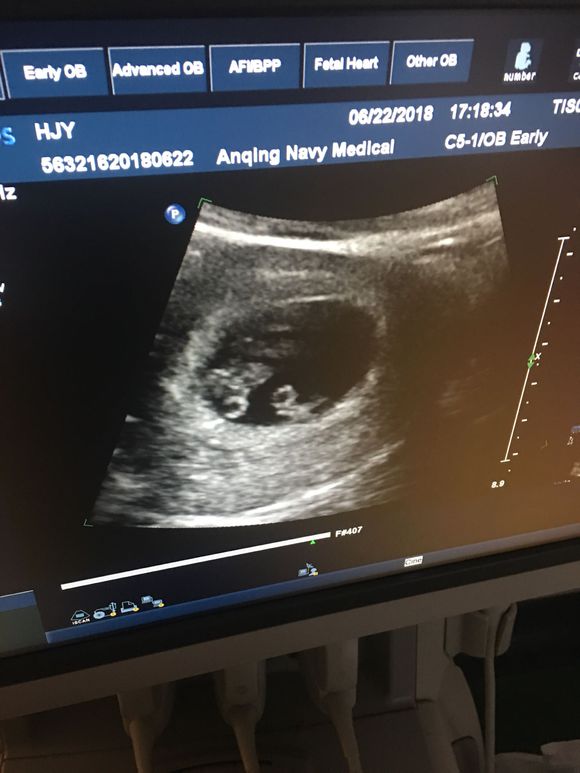

8月16日Z先生打来电话报喜说说太太怀的是双胞胎,家里老人也非常高兴并在电话中对我们孕达国际医疗表示感谢,说再也不是“单传“了。给孕达国际医疗报喜.